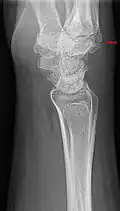

Carpometacarpal bossing

Carpometacarpal bossing (or metacarpal/carpal bossing) is a small, immovable mass of bone on the back of the wrist. The mass occurs in one of the joints between the carpus and metacarpus of the hand, called the carpometacarpal joints, where a small immovable protuberance[1] occurs when this joint becomes swollen or bossed.

The joint between the index metacarpal and the capitate is a fibrous non-mobile joint. Some people have a gene that leads to this growth. It looks like arthritis (bone spurs on each side of the joint) on X-ray. It looks like a ganglion on the hand, but more towards the fingertips.

The carpometacarpal joint is usually found at the base of the second and third metacarpal bones at the point where they meet the small bones of the wrist.[2]